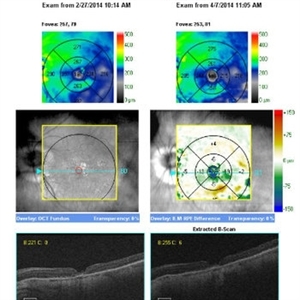

Macular Hole

Macular Hole

Jul 1 2014 by John S. King, MD

High myope c history of mac-off rrd c inf tear and ftmh that appeared chronic on presentation. RD repaired, hole remained open. ILMx performed with inverted flap. One and three months s/p MHx.

Photographer: Wayne A Ladlee Jr

Imaging device: Cirrus

Condition/keywords: macular hole, myopic degeneration